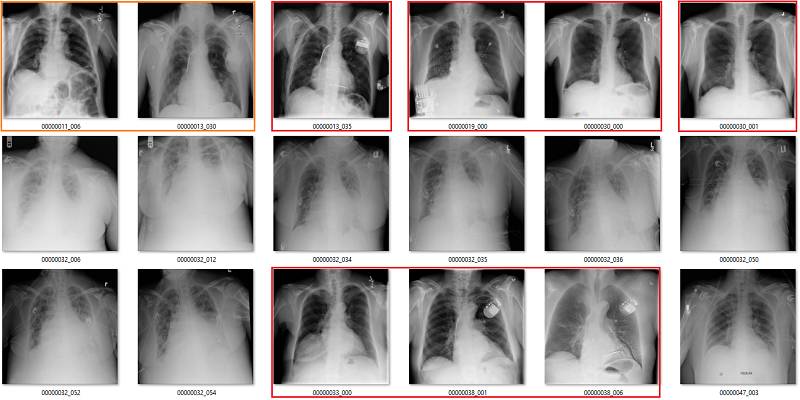

这部分要说该数据集中基于标签的图像。它们是随机选取包含 18 张图像的序列集,并非精挑细选。

我尽量保持谨慎,当一个案例模棱两可的时候,我选择标出标签类别。在所有图像中,红色 = 明显错误的标签;橙色 = 怀疑态度,我没有指出这个问题,但是不能排除这种怀疑。(出于临床诊断的习惯 :p)

肺不张(Atelectasis)